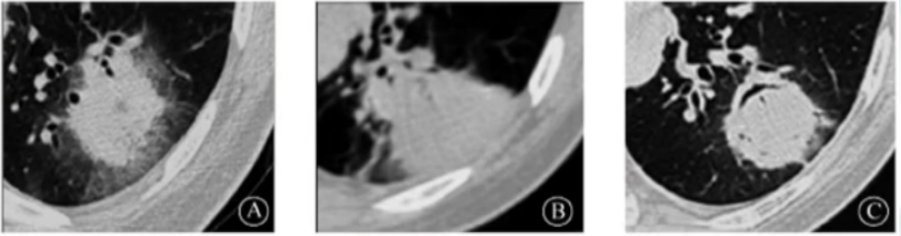

粒缺患者常见晕轮征、楔形改变和空气新月征等特异性改变(图2),非粒缺患者常见实变、结节、空洞、树芽征、中央型支气管扩张等非特异性改变(图3)

图片

2  粒缺IPA患者影像学表现

粒缺与非粒缺患者IPA影像学改变的差异与发病机制不同有关。对于免疫功能缺陷(例如粒缺)患者,曲霉为所欲为,在肺部的各个部位发起进攻,破坏肺组织;气道壁增厚,或引起大片实变小的气腔结节、树芽征、腺泡结节,也可以融合成团;血管受累,主要是血管炎、出血、栓塞、坏死,表现为晕轮征、空气新月征、楔形实变。而在免疫功能正常患者中,曲霉感染比较局限,很少发展壮大,曲霉只能寻找肺部薄弱之处攻击,首先攻击残存的空洞或空腔,也就是我们常见的曲霉球或CPA。此外,在免疫功能亢进患者中,免疫系统对曲霉的敏感性极高,曲霉一旦进入气道内就会立刻被发现,在大气道内筑起强大的防护屏障,仅在大气道内引起病变和相应的反应,多为曲霉引起的免疫反应改变。